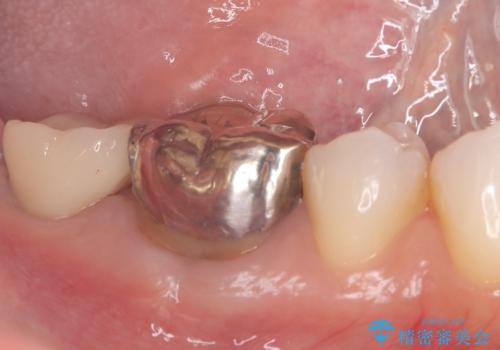

- 患者様は、奥歯を失ったことで「しっかり噛めるようになりたい」とのご希望で来院されました。ブリッジや入れ歯ではなく、インプラントによる治療を希望されたため、精密検査を実施。骨の状態が良好であったため、1回法(1回の手術でインプラント埋入とヒーリングアバットメント装着を同時に行う方法)を選択しました。これにより、外科的負担を軽減しながら、治療期間の短縮も図ることができました。

手術は1回で完了し、局所麻酔下でインプラントを埋入した後、ヒーリングアバットメントを装着。術後の腫れや痛みも少なく、患者様はスムーズに日常生活へ戻ることができました。約3ヶ月の治癒期間を経て、セラミッククラウンをセット。見た目の美しさはもちろん、天然歯に近い噛み心地を実現しました。患者様からは「違和感なくしっかり噛める」とご満足の声をいただきました。